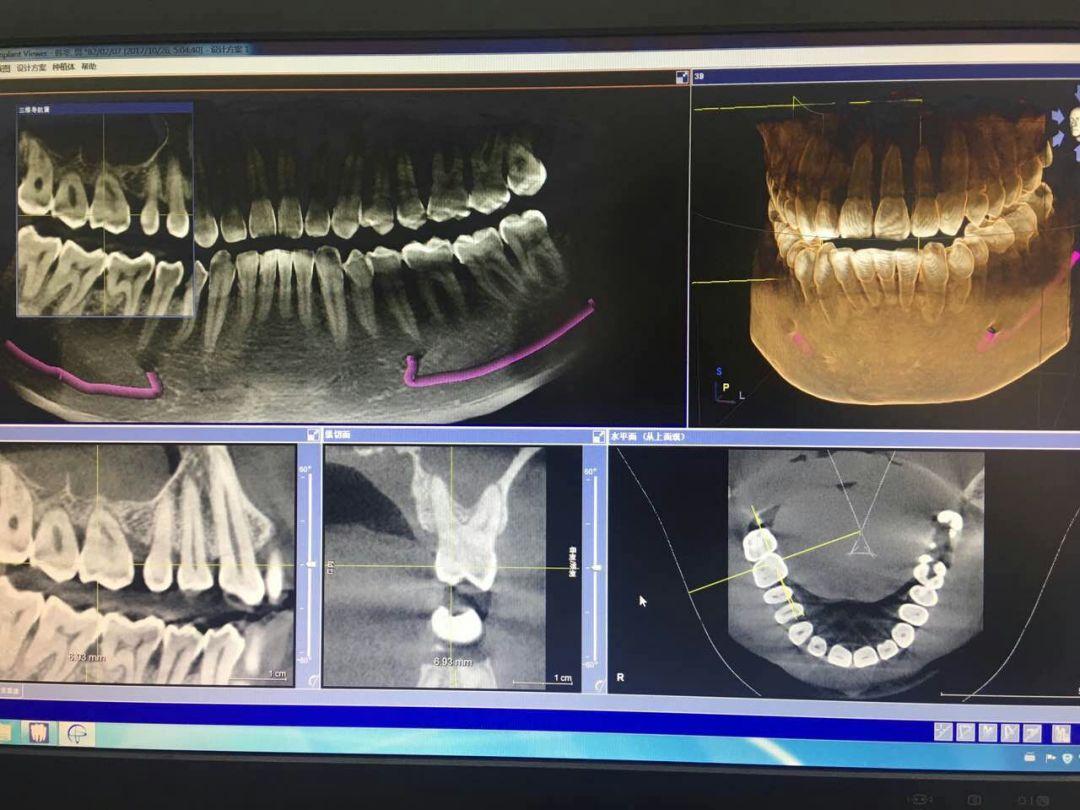

CBCT掃描可準確分析頜骨植入?yún)^(qū)的骨質(zhì)、骨量、骨密度及植體與下頜神經(jīng)管、上頜竇的關(guān)系,臨床醫(yī)生可以在圖像上模擬種植,直接與患者進行溝通及交流,并可指導手術(shù)者在手術(shù)方案中避開危險區(qū)域,手術(shù)的性。此外,臨床醫(yī)生還可以利用CT數(shù)據(jù)進行數(shù)字模型重建,配合軟件預(yù)先做好手術(shù)模板使種植手術(shù)更快捷。